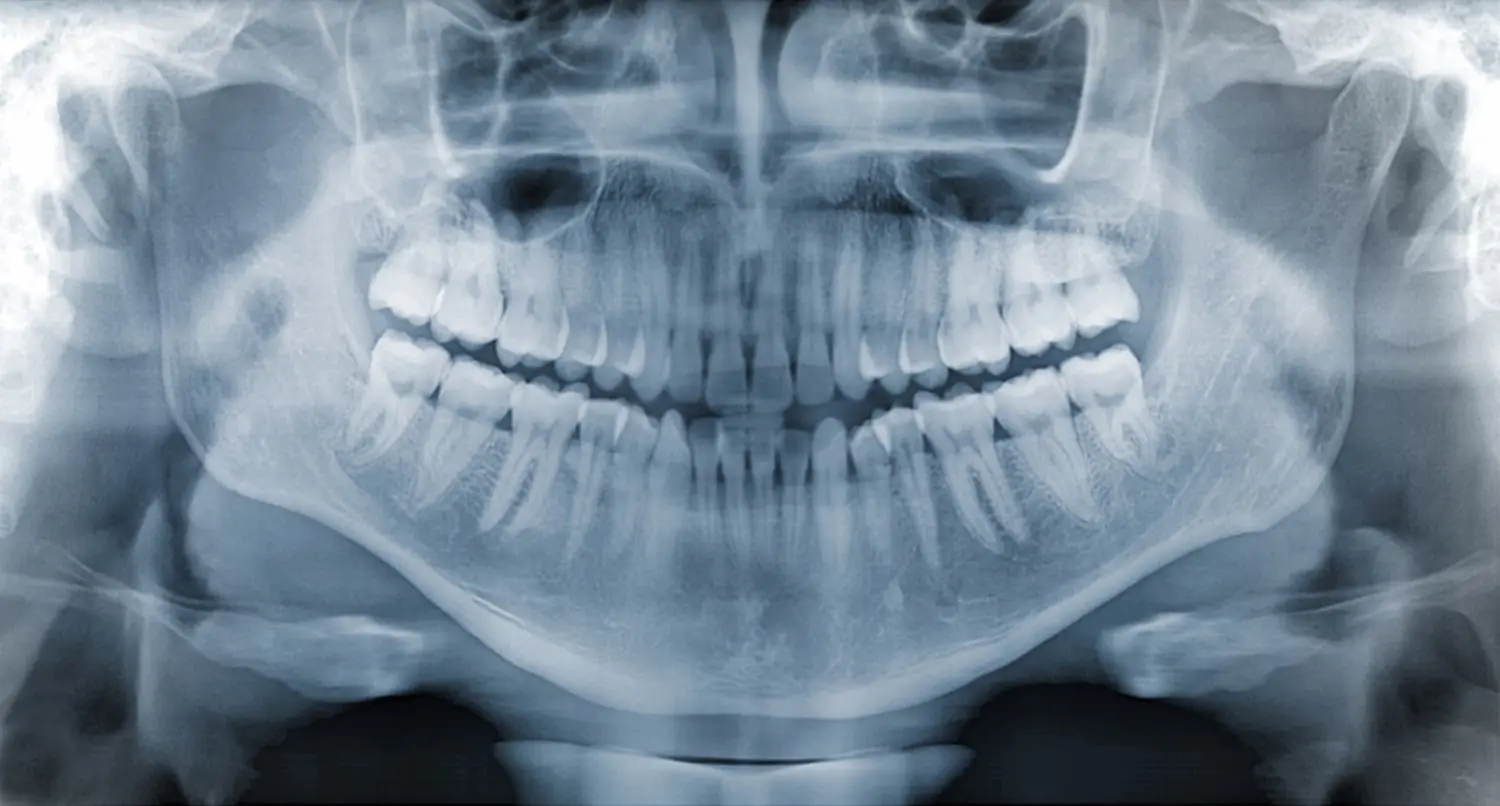

Advanced digital X-ray technology provides detailed images of your teeth, roots, and surrounding structures with significantly reduced radiation exposure compared to traditional film X-rays. Some patients have concerns about X-ray safety, which is why our state-of-the-art digital radiography systems are essential for accurate diagnosis while prioritizing your safety and comfort.

Modern dental X-rays represent a vital diagnostic tool that allows our dental team to see beyond what's visible during a clinical examination. Many oral health issues develop internally or between teeth where they cannot be detected with visual inspection alone. Digital X-rays reveal these hidden problems, enabling early detection and treatment.

Our digital X-ray systems provide numerous advantages over traditional film radiography. Digital sensors capture images instantly, eliminating the need for chemical processing and providing immediate results. The images can be enhanced, enlarged, and manipulated on computer screens for better visualization of potential problems. Most importantly, digital X-rays use up to 90% less radiation than conventional film X-rays while producing superior image quality.

The types of dental X-rays we offer include bitewing X-rays for detecting cavities between teeth, periapical X-rays for examining individual tooth roots and surrounding bone, and panoramic X-rays for comprehensive views of all teeth, jawbones, and surrounding structures. Each type serves specific diagnostic purposes and may be recommended based on your individual oral health needs.